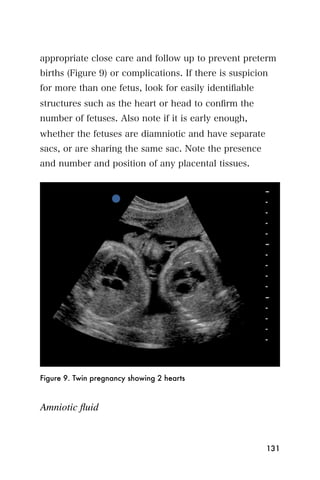

Again, the ejection fraction is evaluated by the operator

and is usually just estimated. Estimating the ejection

fraction comes with practice, but after reviewing a few

echocardiograms and performing a few echocardio-

grams, the operator should be able to identify patients

with a normal EF and patients with a low EF.

Apical four chamber view